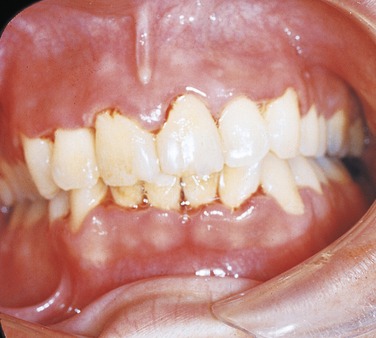

PLATE 4 Necrotizing ulcerative gingivitis.